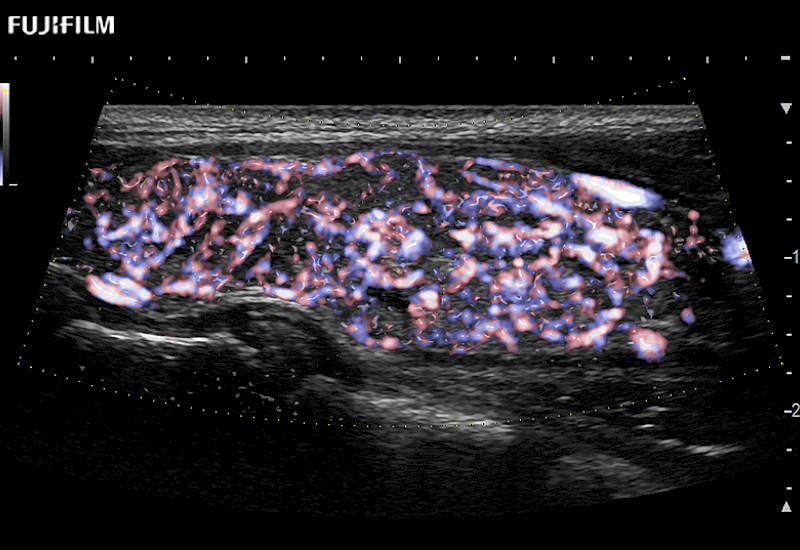

Fujifilm Healthcare understands that Surgical Oncologists demand excellence in their operating rooms — from their staff and the equipment they depend on. Fujifilm Healthcare's dedication to Surgical Oncologists provides outstanding ultrasound technology, professional support and the specialized tools necessary to best perform comprehensive real-time ultrasound imaging.

For precise surgical oncology ultrasound imaging, Fujifilm Healthcare offers premium level solutions that include:

for use during open and laparoscopic procedures: Tumor localization & staging, Ablation, Resection, Biopsy, Transplant, Abdominal exploration, Robotic surgery

Our dedication to Surgical Oncology allows us to offer superior image quality, outstanding system reliability and intuitive use of cutting edge technology.